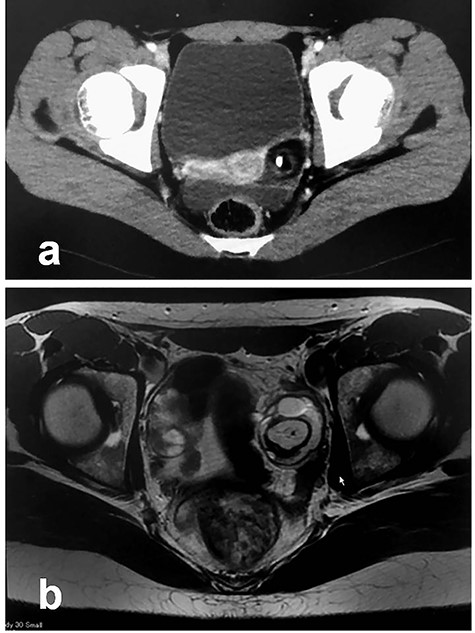

Patient 1: In a 12-year-old girl with abdominal pain, enhanced computed tomography (CT) showed a swollen appendix and a left ovarian mass; she was diagnosed with appendicitis (Fig. 1a). After laparoscopic appendectomy, she underwent magnetic resonance imaging (MRI), which revealed an ovarian MCT (38 cm × 30 cm; Fig. 1b). She underwent a second procedure, laparoscopy-assisted extracorporeal cystectomy (a hybrid, minimally invasive approach), during which the tumor was placed in a specimen retrieval bag and exteriorized through a suprapubic incision. The tumor was then excised, and the ovary returned to the pelvis. There was no content spillage (Fig. 2). The excised margins of the tumor were continuously oversewn using absorbable suture. Pathologic examination confirmed the diagnosis of MCT. The patient has been doing well without evidence of recurrence. She subsequently established a regular menstrual cycle.

Patient 2: In a 14-year-old girl with abdominal pain, enhanced CT showed a left ovarian tumor (Fig. 3a). Further examination, including MRI, revealed an ovarian MCT (70 cm × 67 cm; Fig. 3b). She underwent laparoscopic surgery, during which the tumor was placed in a specimen retrieval bag. The contents were aspirated using a newly developed soft-cup aspirator set (Hakko Co., Tokyo, Japan) [9], and the tumor was excised without content spillage (Fig. 4). The excised margins were continuously oversewn using the V-Loc™ absorbable wound closure device (Covidien Healthcare, Minneapolis, MN). Pathologic examination confirmed the diagnosis of MCT. She has been doing well without evidence of recurrence. She subsequently established a regular menstrual cycle.